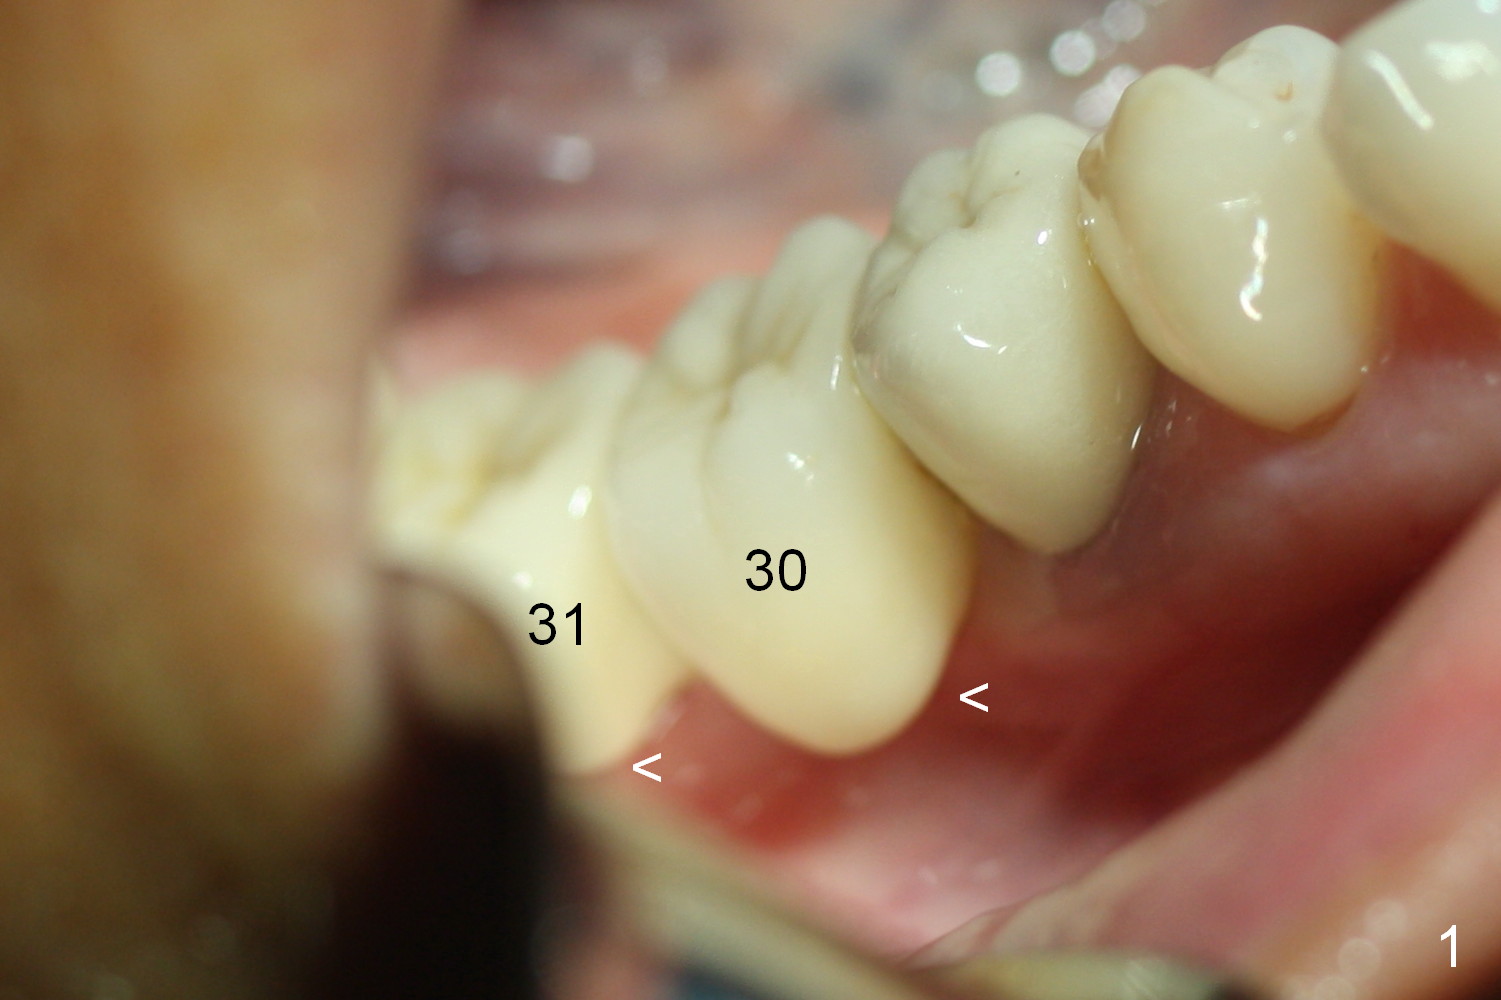

A preop photo shows different shape of pontics at #30 and 31 (Fig.1 <), suggesting different width of the edentulous ridge. Two of 8 mm parallel pins are inserted for position and trajectory (Fig.2 (red dashed line: the superior border of the Inferior Alveolar Canal). When they are removed from the osteotomy sites, the narrow ridge at #30 is shown (Fig.3). A 3x12 mm 1-piece implant is placed at #30, while a 4.5x10 mm 2-piece one at #31 (Fig.4,5). It appears that it is necessary to place an implant at #32, since the tooth #1 is present (Fig.5). The suggestion is rejected by the patient due to finance. After extraction of the tooth #32 and insertion of collagen plug, an immediate splinted provisional is fabricated to cover the #32 socket as well (Fig.6). The provisional is modified (to remove the portion that covers #32 socket) 3-4 weeks postop.